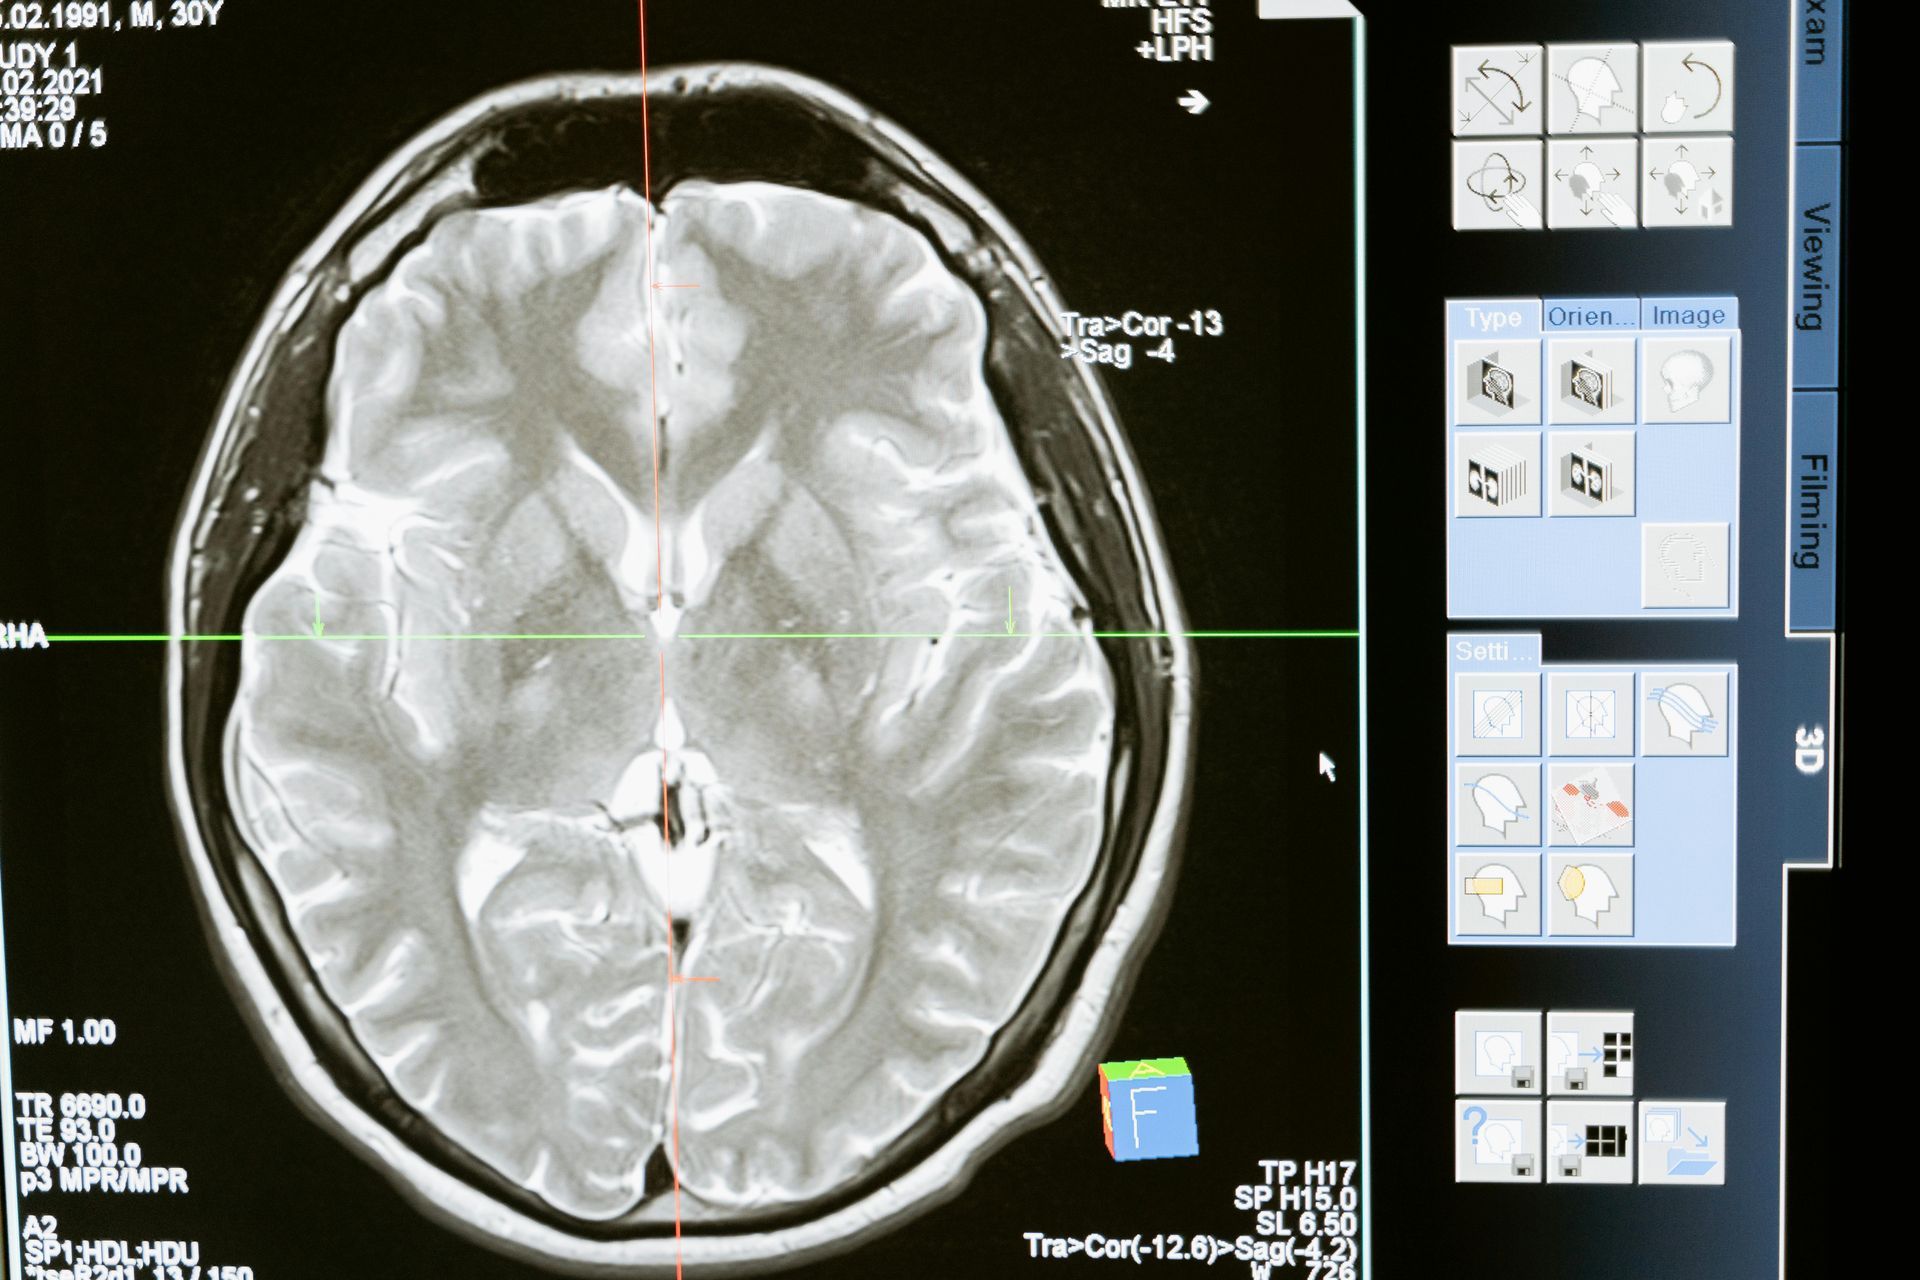

- Tecnología médica de vanguardia

Electroencefalograma (EEG)

Es un estudio no invasivo que registra la actividad cerebral. Fundamental para el diagnóstico de epilepsia, trastornos del sueño, encefalopatías y otras afecciones neurológicas. Se realiza en un ambiente cómodo y con interpretación profesional del especialista.